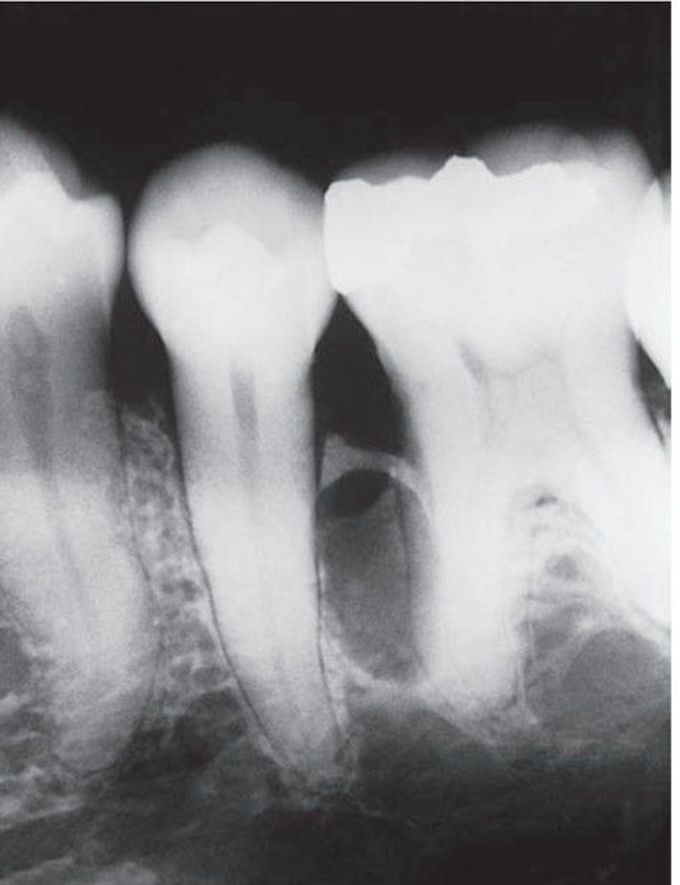

Lateral periodontal cyst associated with 2nd premolar

Adults; lateral periodontal membrane, especially mandibular cuspid and premolar area.